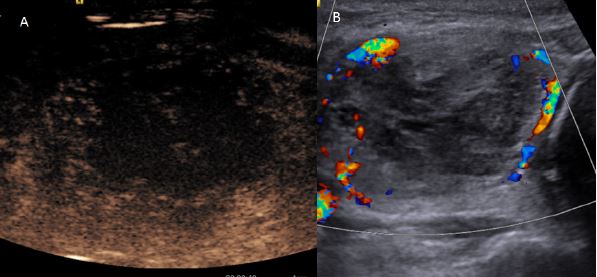

Para los procedimientos se utilizó láser Nd-YAG (neodimiumyttrium aluminium garnet) con una longitud de onda 1.064 mm (EchoLaser X4 ©, Esaote, Génova, Italia). El tratamiento AL-LF se realiza con el paciente en decúbito supino y el cuello en hiperextensión. Durante el procedimiento se introduce bajo control ecográfico una aguja guía con calibre de 21 G a lo largo del diámetro cráneo-cadual del nódulo tiroideo (Fig.1) o realizando un abordaje latero- lateral (Fig.2). La elección del abordaje varía en función de la morfología del nódulo y de sus relaciones con las estructuras anatómicas cervicales adyacentes.

Cuando la punta de la aguja se encuentra correctamente posicionada a nivel intralesional, se introduce en la aguja guía una fibra óptica de 300 μm hasta que los 7 mm distales de la fibra óptica encuentren en contacto directo con el tejido tiroideo, respetando unos limites de seguridad de 10 mm respecto a la

capsula tiroidea. Las iluminaciones láser se realizan a través de una fuente de energía de 3 W. AL-LF consiste en la realización sucesiva de múltiples iluminaciones láser superpuestas, de baja y media energía que varía entre 300 a 1.000 Julios (J), utilizando una única fibra óptica activa que se mueve de forma secuencial en el nódulo tiroideo objeto del tratamiento ( Fig.3). Al final de cada iluminación bajo control ecográfico y utilizando la técnica de mano libre se reposiciona la punta activa de la fibra óptica a nivel intranodular y se realiza una nueva iluminación en la parte del nódulo adyacente al área tratada previamente ( Fig.4) . La longitud de la recolocación de la punta de la aguja depende de la energía suministrada en cada iluminación. El número total de los reposicionamientos de la